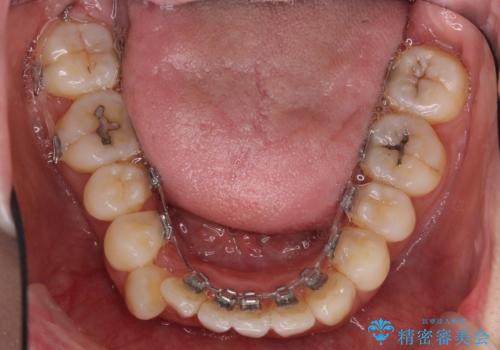

- リンガルブラケット

上顎の前から4番目の歯を両側抜歯して、上下裏側の装置で前歯を引っ込める計画としました。

裏側からの矯正であったため、表側に比べて少し治療期間を要しました。